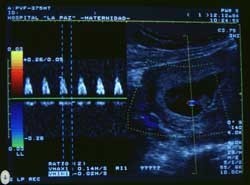

La técnica doppler es un ecografía a color, que se utiliza para medir y evaluar el flujo de sangre que circula a través de las cavidades y las válvulas del corazón del bebé.

Permite saber la cantidad de sangre que se bombea con cada latido, lo cual es fundamental para determinar el buen funcionamiento de su corazón, así como para analizar las válvulas cardíacas y las paredes del corazón.

La ecografía doppler también se utiliza para ver las arterias uterinas en casos de mujeres con riesgo de hipertensión durante el embarazo o cuando hay sospecha de retraso de crecimiento intrauterino.

Se controlan también las arterias umbilicales para asegurarse de que el flujo de sangre y por ende los nutrientes y el oxígeno están llegando adecuadamente al bebé.